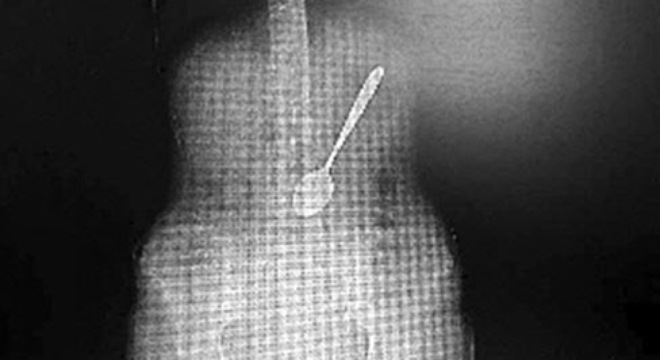

Bác sĩ Ấn Kiện cho biết, qua kiểm tra ông phát hiện trong dạ dày của cô Vương có một chiếc thìa inox dài khoảng 15cm, tình trạng nghiêm trọng hơn nhiều so với những gì các bác sĩ nghĩ ban đầu.

Qua ảnh chụp CT bác sĩ đã phát hiện ra chiếc thìa dài hơn 15cm trong bụng cô Vương và nằm chếch một góc 30 độ. Theo bác sĩ, chiếc thìa có thể trượt vào ruột bất cứ lúc nào. Và nếu điều đó xảy ra, chiếc thìa có thể làm thủng dạ dày gây tổn thương tới nội tạng, thậm chí có thể dẫn tới tử vong. Từ đó, các bác sĩ đã quyết định nhanh chóng lấy chiếc thìa ra ngoài.